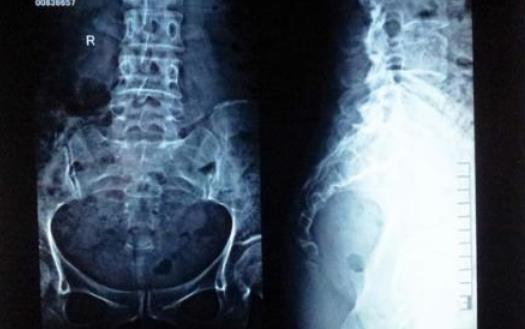

尾骨其实就是人类的“尾巴”,随着人类的进化,尾巴的作用越来越小,最终“退化”到如今的结构,看起来像是三角形。由于生理结构的不同,女性尾骨比男性的更小、更低一些,所受压力更大,因而女性更容易出现尾骨疼痛。